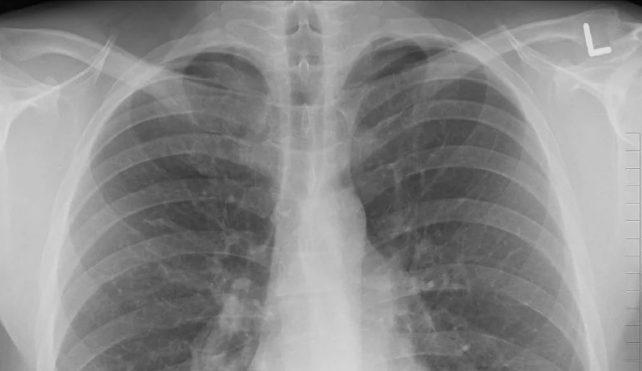

مؤسسه ملی سرطان اعلام کرد که پنج نوع سرطان در مالزی شایعتر هستند، شامل سرطان سینه، سرطان روده بزرگ یا کولون، سرطان ریه، سرطان نازوفارنکس یا سر و گردن، و سرطان کبد.